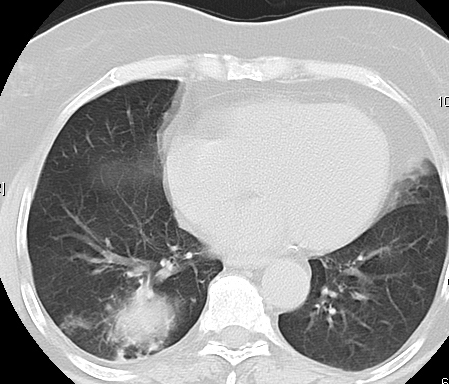

Foto: Aleksandar Ivković Foto: Aleksandar Ivković Foto: Aleksandar Ivković Strašna razlika kod pluća pušača i kovid pozitivne osobe autor: Božica Luković Zdravlje 23. jan. 2021. 12:06 > 23. jan. 2021. 12:15 0 Podeli vest: Radiolog Aleksandar Ivković od početka pandemije daje korisne informacije o svim aspektima kovida 19. On je nedavno uporedio rendgen snimke pluća zdrave osobe, pušača, osobe koja je zaražena gripom H1N1, a onda i osobe koja ima kovid 19. Razlike su zapanjujuće. Podeli vest: Oglas Objavu doktora Ivkovića sa njegovog bloga "Ljudi i ostale laži" prenosimo u celosti."Nedavno sam video u medijima da je neko preneo rdg sliku i razlike kod nalaza zdrave osobe, pušača i bolesnog od kovida 19. Kako nisam baš previše zadovoljan onim što je prikazano, evo kako to izgleda u našoj varijanti. Zdrava osoba CT nalaz kod zdrave osobe podrazumeva da ne postoje nikakvi poremećaji strukture plućnog parenhima, da su krvni sudovi uredni i da nema suženja disajnih puteva, kao i da nema uvećanih limfnih žlezda u hilusima pluća i medijastinumu. Foto: Aleksandar Ivković | Foto: Aleksandar Ivković * Foto: Aleksandar Ivković | Foto: Aleksandar Ivković Zdrava muška osoba mesec dana nakon zapaljenja pluća tokom kovida 19. Nalaz bez nekih posebnih problema iako se naziru tragovi zapaljenja. Snimak u boji je zdrava osoba, nepušač, bez ikakvih bolesti pluća u istoriji. Grip H1N1 Pokazaću samo drastične nalaze kod gripa H1N1, to je znači onaj grip koji je izazvao epidemiju španske groznice i epidemiju 2009. godine koja još uvek nije prestala (svake godine imamo makar 15%). Foto: Aleksandar Ivković | Foto: Aleksandar Ivković * Foto: Aleksandar Ivković | Foto: Aleksandar Ivković * Foto: Aleksandar Ivković | Foto: Aleksandar Ivković * Foto: Aleksandar Ivković | Foto: Aleksandar Ivković Nisu svi pacijenti imali ovakve nalaze, pokazujem one koji su imali tešku kliničku sliku. Kod gripa se sve odvija obično u sedam dana. Kao što se vidi, zapaljenje je bilo jednostrano, uglavnom. Ali kada je dolazilo do pogoršanja, onda je centralno obostrano dolazilo do edema pluća. Pušenje Kod pušača postoje razne varijante nalaza na plućima. U principu nisu tako dramatične kao što su zapaljenja. Nalaz na plućima kod pušača može biti potpuno normalan. Ovo ne pišem zato što podržavam pušenje, naprotiv, veliki sam protivnik, ali iznošenje laži nikada nije dobro. Dve dijagnoze su bitne kao posledica pušenja. Prva je hronična plućna opstruktivna bolest: Foto: Aleksandar Ivković | Foto: Aleksandar Ivković * Foto: Aleksandar Ivković | Foto: Aleksandar Ivković * Foto: Aleksandar Ivković | Foto: Aleksandar Ivković Jasna je razlika u nalazu, posebno na ovim slikama u boji, gde su ta plava polja delovi pluća koji su propali zbog cigareta (može da se uporedi sa zdravim plućima iznad).Druga bolest koja je česta kod pušača je u svakom slučaju karcinom. Foto: Aleksandar Ivković | Foto: Aleksandar Ivković * Foto: Aleksandar Ivković | Foto: Aleksandar Ivković * Foto: Aleksandar Ivković | Foto: Aleksandar Ivković * Foto: Aleksandar Ivković | Foto: Aleksandar Ivković Tkivo koje raste unutar pluća i razjeda ga. Takav je nalaz kod karcinoma pluća. Često je uzrok upotreba cigareta. Kovid 19 O kovidu sam pisao puno puta. Evo nekih slika, radi poređenja. Foto: Aleksandar Ivković | Foto: Aleksandar Ivković * Foto: Aleksandar Ivković | Foto: Aleksandar Ivković * Foto: Aleksandar Ivković | Foto: Aleksandar Ivković * Foto: Aleksandar Ivković | Foto: Aleksandar Ivković Nakon što pacijent bude izlečen od gripa ili kovida 19, pluća se mogu vratiti u normalu.To je razlika u odnosu na posledice upotrebe cigareta. Ovi snimci nisu postavljeni da bi se poredile bolesti, već da bi se ukazalo kako različite bolesti deluju na pluća. I ono što je veoma važno, ako neko dobije jednu od ovih bolesti, ne znači da u toku života neće dobiti drugu.Ne pišem zato smo smatram da sam najpametniji ili najpozvaniji da objašnjavam, nisam kao neki pojedinci ubeđen da samo ja imam znanje i istinu, pišem jer drugi ćute. Pišem jer ima i puno onih koji iznose laži, mora se tome stati na put.A ovi, koji pišu da sam umro, da sam oboleo od karcinoma, ovi koji mi žele da nađem dobro grobno mesto, šta da vam kažem, vi ste mi inspiracija. Svesni ste da sam u pravu i odlično znam da ste već uradili sve da se vakcinišete i mnogi od vas će to uraditi pre mene ali i dalje ćete ubeđivati druge da se ne vakcinišu i da je dobro za njih da se razbole i umru. Ima puno reči za vas u svim našim slovenskim jezicima, znate vi sami šta ste", piše dr Ivković.***Bonus video:https://youtu.be/MWucTT0qBsIPratite nas i na društvenim mrežama:FacebookTwitterInstagram Dr Lukić otkrio spisak svih antibiotika za kovid upalu pluća Zdravlje 0 Dr Žujović: Kako oporaviti pluća posle korone Zdravlje 0 Pet znakova da ti je kovid zahvatio pluća Zdravlje 0 Virusolog Ana Banko ruši veliku zabludu o ruskoj vakcini Emisije 0 aleksandar ivković korona kovid pluća snimak pluća Pratite nas na društvenim mrežama: Koje je tvoje mišljenje o ovoj temi? Učestvuj u diskusiji ili pročitaj komentare Budite prvi koji će ostaviti komentar Pošalji komentar Pročitaj komentare (0)